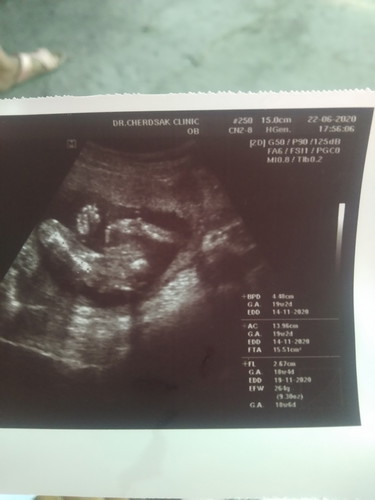

ทีมเดือนพ.ยแม่บ้านนี้ซาวหมอแรกบอกผ.ญ.90/:พอซาวอีกหมอหมอบอกว่าผ.ช100/:เห็นเพศชัดเจนให้แม่ๆๆช่วยดูภาพซาวหน่อยว่าชหรือญดูไม่ออกจริงๆค่ะ